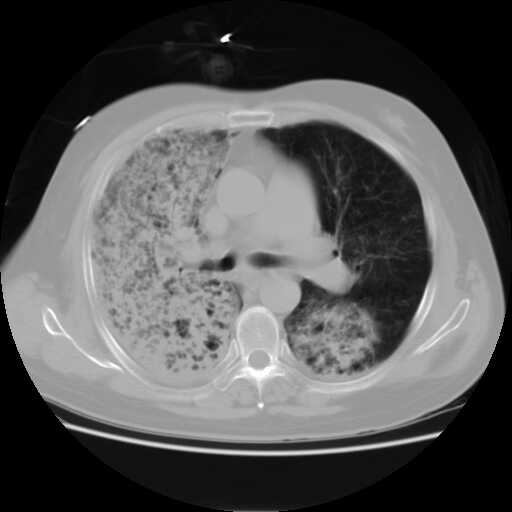

2008.8.17ct定位片

2008.8.17ct

病变从8.11-8.17明显改变,增多,以蜂窝状改变为主,类蜂窝肺,似弥漫性肺泡癌,但是病变进展太快,不符合弥漫性细支气管肺泡癌。因此考虑为特殊微生物感染,多以霉菌类常见,建议细菌微生物学检查。

疑点二:影象表现怪异,大片阴影内见多发筛孔征,如何解释.